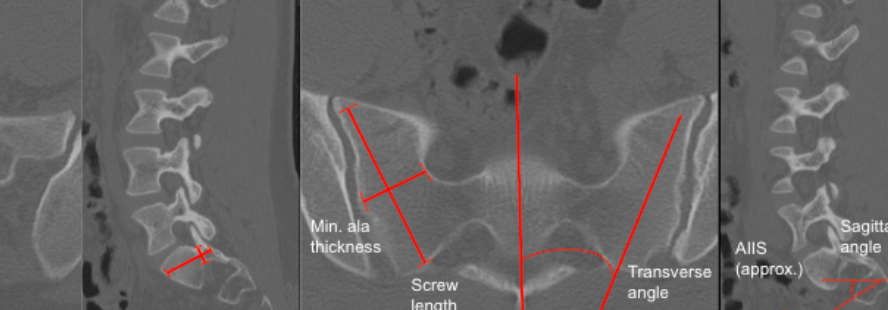

Sacral Morphometry